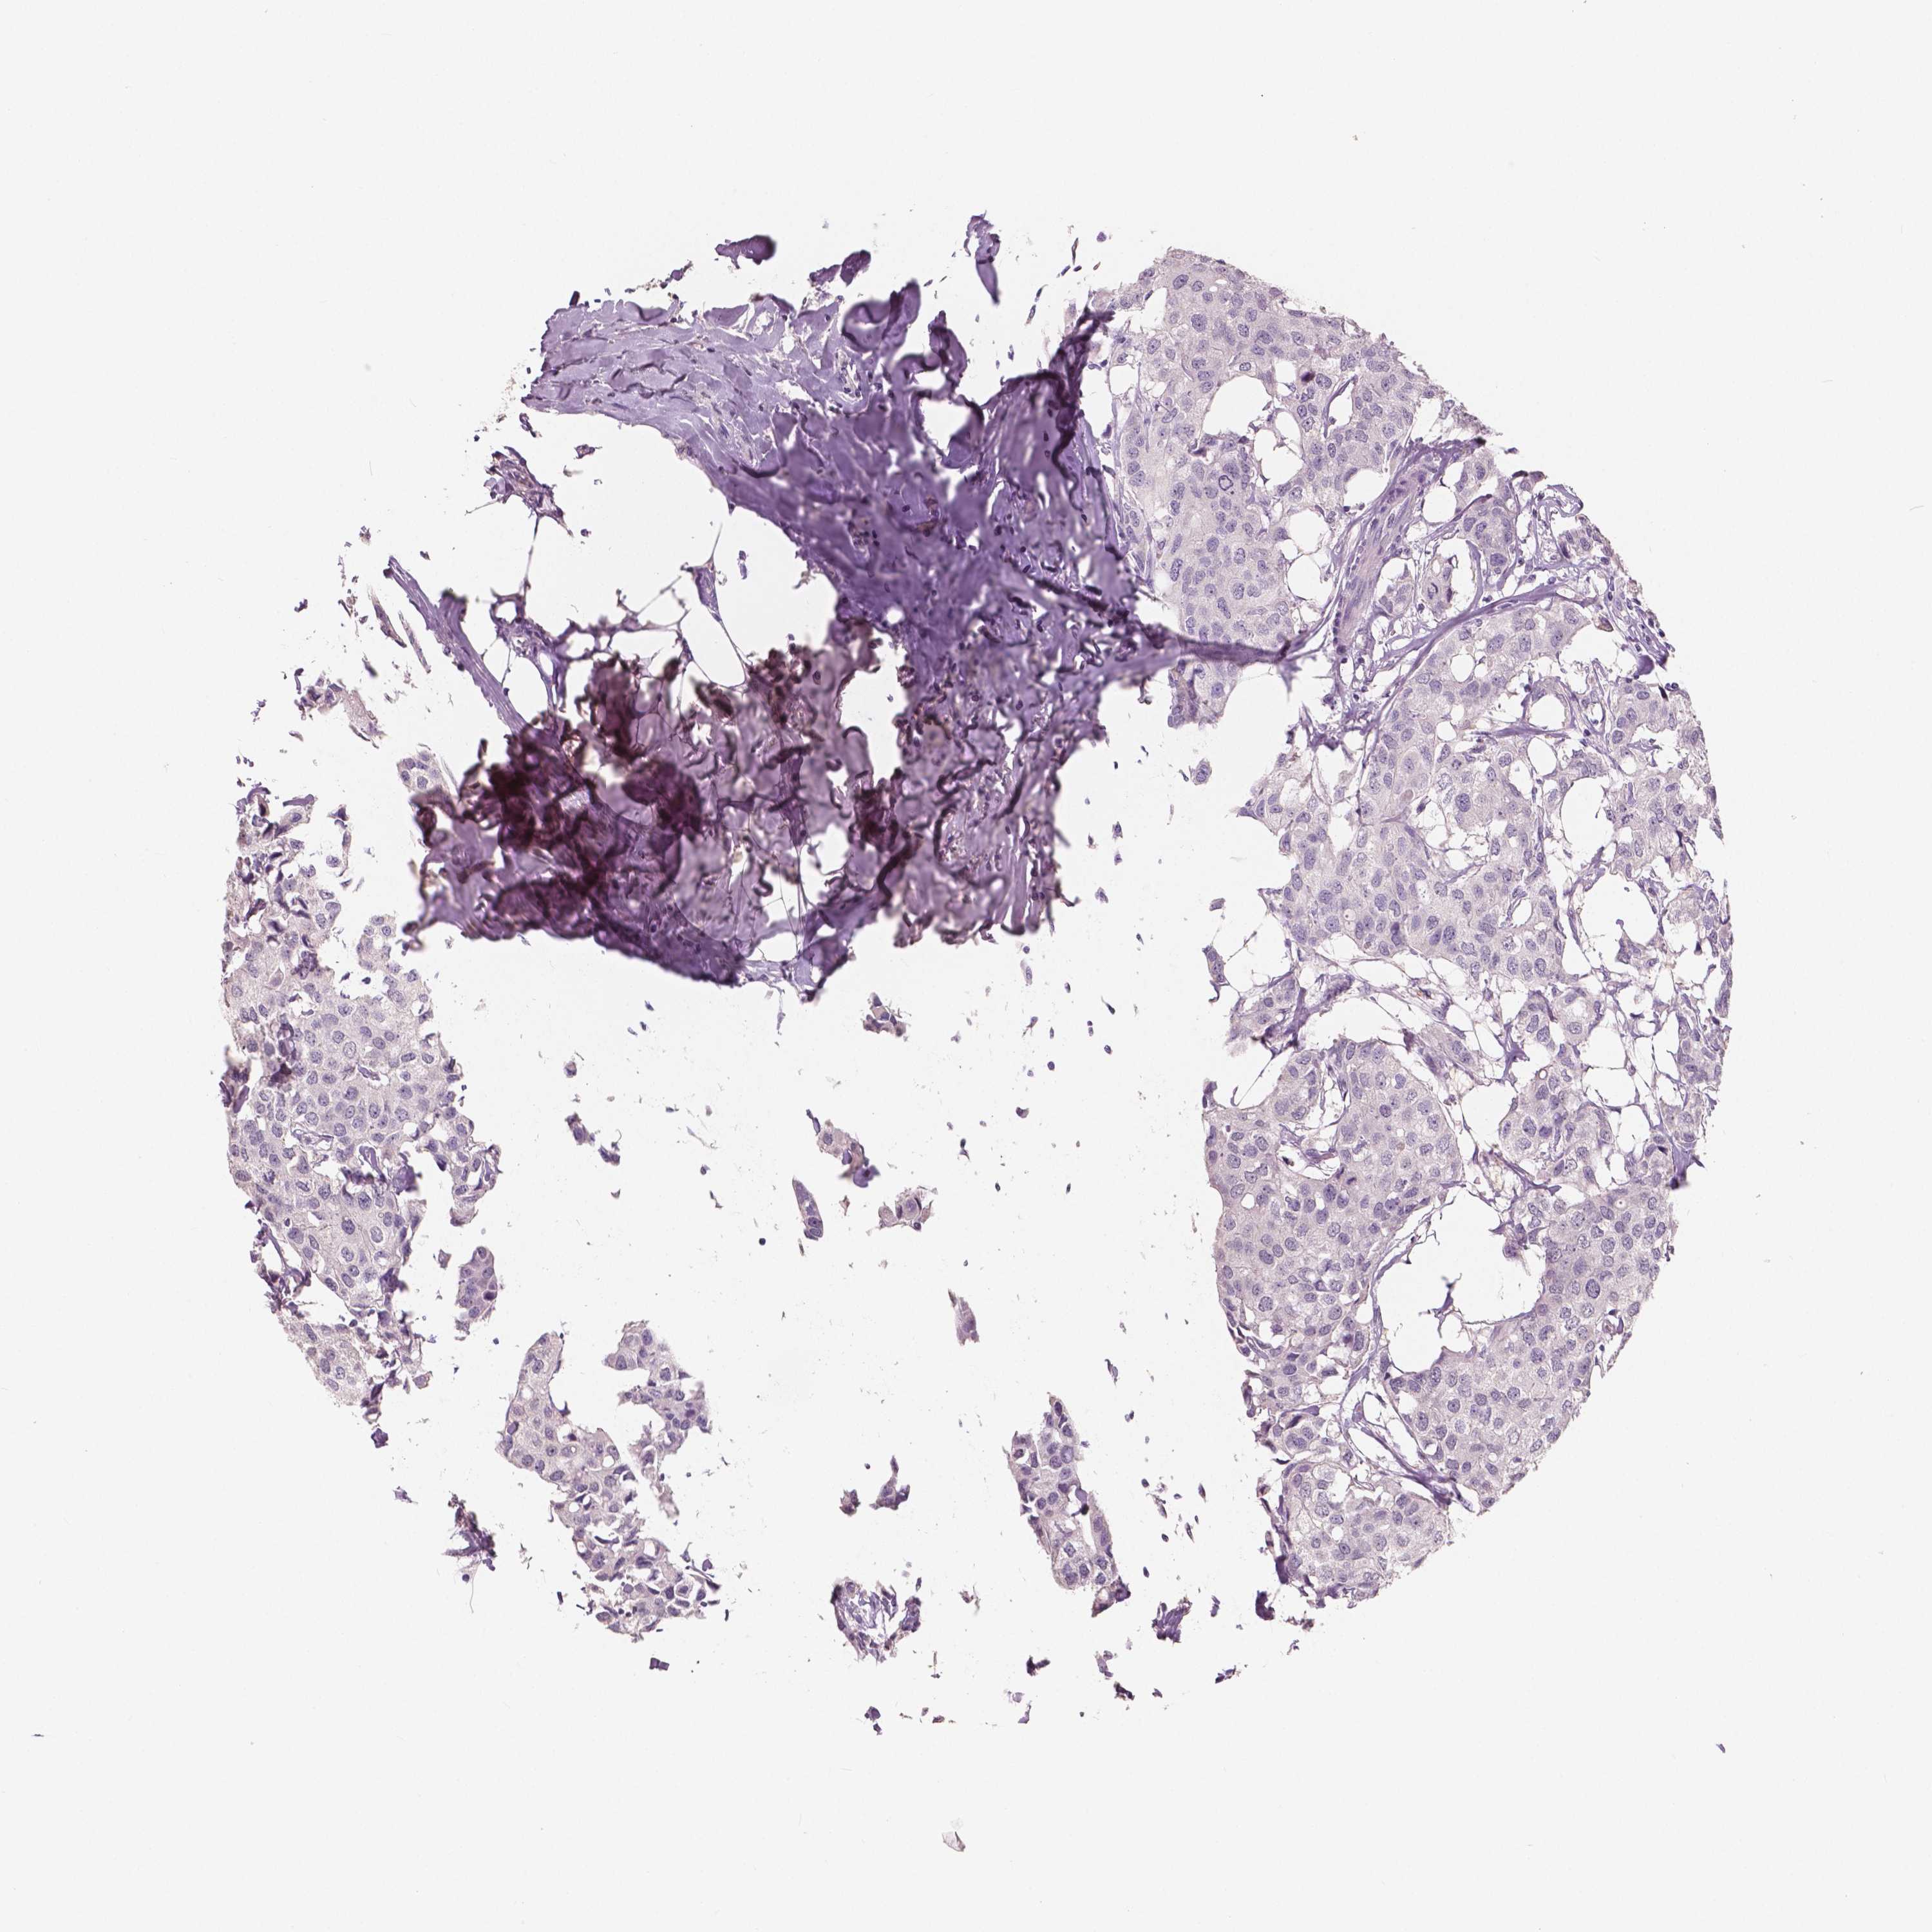

CANCER BREAST CANCER Show tissue menu

Breast cancer

Human cancer